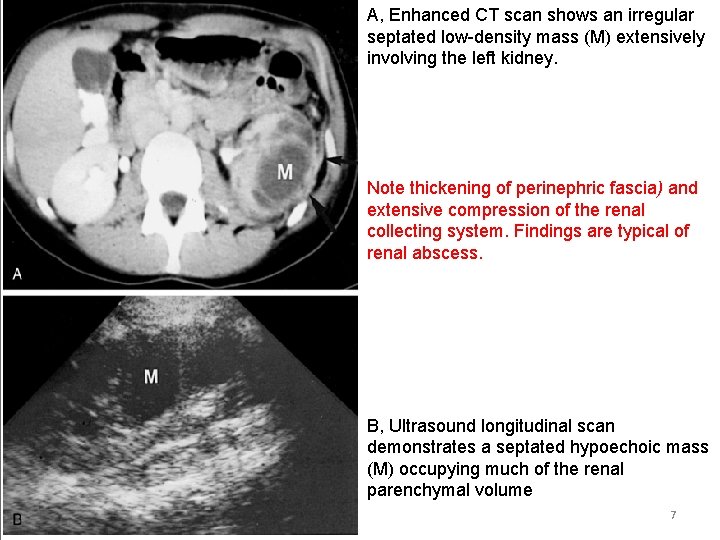

A, Enhanced CT scan shows an irregular septated low-density mass (M) extensively involving the left kidney. Note thickening of perinephric fascia) and extensive compression of the renal collecting system. Findings are typical of renal abscess. B, Ultrasound longitudinal scan demonstrates a septated hypoechoic mass (M) occupying much of the renal parenchymal volume 7